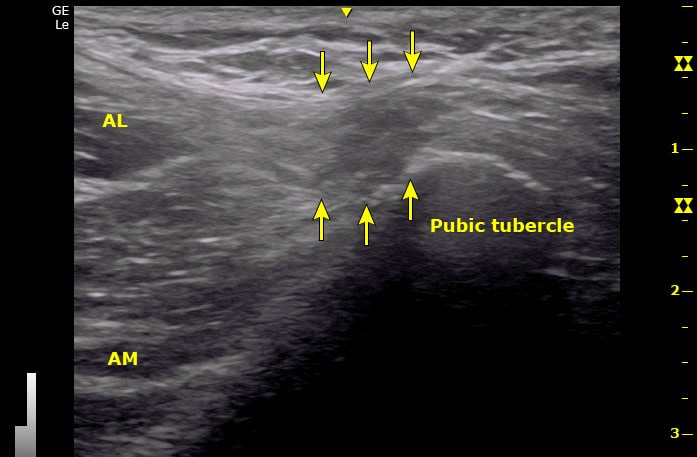

- Músculos adutores: deve-se avaliar a inserção tendínea e a junção músculo-tendínea dos adutores, com ênfase no adutor longo. A presença de espessamento, hipoecogenicidade (sinal de inflamação) e irregularidades tendíneas pode indicar tendinopatias.

- Sínfise púbica: o exame avalia a articulação púbica e a presença de sinais de inflamação ou lesões, como o espessamento da cartilagem articular ou erosões ósseas.

Achados ultrassonográficos da pubalgia

Tendinopatia dos adutores

Visualizada como espessamento e hipoecogenicidade do tendão do adutor longo. Em casos avançados, podem ser observadas calcificações ou descontinuidade do tendão.